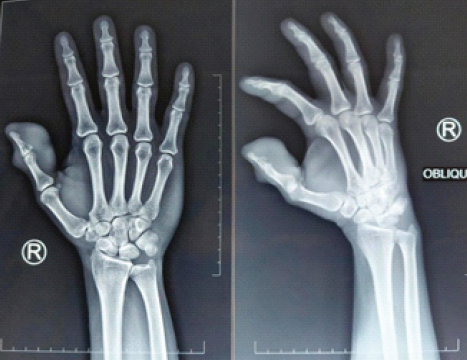

Initial plain radiographs (anteroposterior and oblique) of the right hand demonstrated significant soft-tissue swelling around the thumb, along with pressure erosion (scalloping) around the distal phalanx of the right thumb (Fig. 3).

Figure 3: Pre-operative X-ray of the right hand (anteroposterior and oblique views) shows soft-tissue swelling over the thumb, along with erosion and scalloping on the distal phalanx of the thumb.